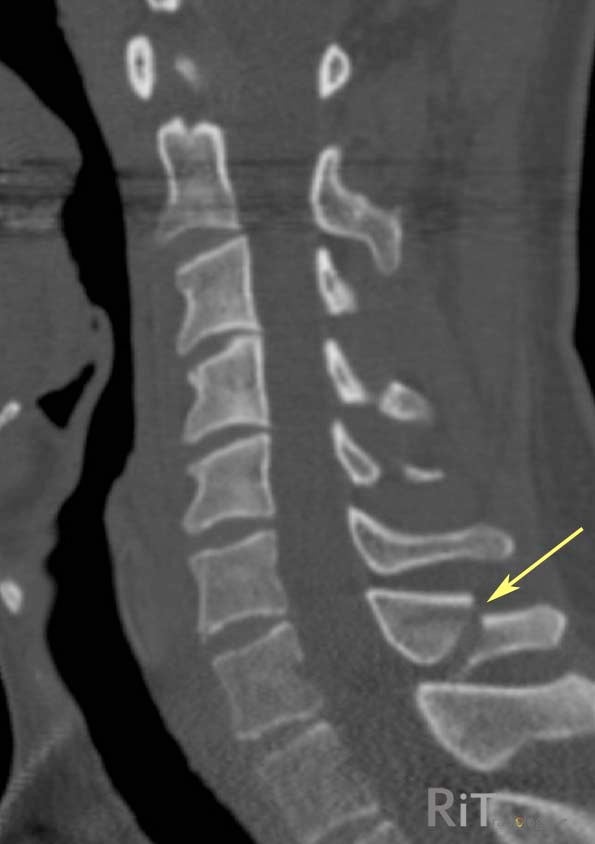

안녕하세요 대구경북(용천, 경산, 경주, 포항, 영덕, 울진, 안강, 왜관, 칠곡, 상주, 금천, 성주, 고령, 안동, 영주, 봉화, 치구) 손해사정사, 손해사정사 Harden Loss Adjustment 입니다. 오늘은 트라우마로 인한 십자돌과 돌기둥의 후유증에 대해 알아보도록 하겠습니다. 횡돌기 또는 횡돌기는 척추 양쪽의 척추 고리에서 확장되는 두 가지 구조로 낙상이나 교통사고와 같은 외상으로 인해 발생합니다. 가시돌기는 좌우 척추뼈가 융합되어 등쪽에서 아래쪽으로 돌출되는 과정입니다. 일반적으로 수술적 치료 대신 보존적 치료를 시행하며, 척추체 자체의 골절이 아니기 때문에 경미한 손상으로 간주되는 경향이 있습니다. 아래 사진에서 두 개의 날개처럼 보이는 것이 횡돌기이고 그 뒤에 가시돌기가 위치한다.

진단에 대한 인식과 환자의 현실 사이에는 불일치가 있습니다. 비수술적 보존적 치료를 하면 바로 입원할 수 있을 만큼 쉬운가요? 그래도 후유증은 정확히 확인해야 한다. 경추, 흉추, 요추의 해당 부위와 골절 정도(다발골절 등), 골절의 종류에 따라 일시적 장애 적용 범위는 18%~24%로 추정 McBride 손실률 테이블. 치료 중에는 활동적이고 집중적인 자세를 유지해야 합니다. 횡돌기 및 극돌기 골절에 대해 궁금하신 사항이 있으시면 아래 링크를 클릭 또는 탭하시면 상담이 가능합니다.